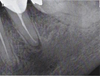

The patient was an 80-year-old woman presenting with a history of coronary stent placement for ischemic cardiopathy, lower left lip in situ squamous cell carcinoma (ipsilateral to the PIOSCC) and a frigore face paralysis. She was treated with acetylsalicylic acid, bisoprolol, glyceryl trinitrate and atorvastatin, was a former smoker and had no allergies. A routine radiographic examination in August 2024 revealed a radiolucent lesion in the left mandibular premolar region (Fig. 1), involving the first and second left lower premolar teeth (20 and 21, using the ADA system). Both teeth had undergone endodontic treatment 10 yr earlier, but a recurrence of apical granuloma was noted on both teeth on the periapical radiograph from May 2024 (Fig. 2). The patient reported no pain, swelling, or any associated systemic symptom.

Fig. 2 Periapical radiograph (May 2024). |